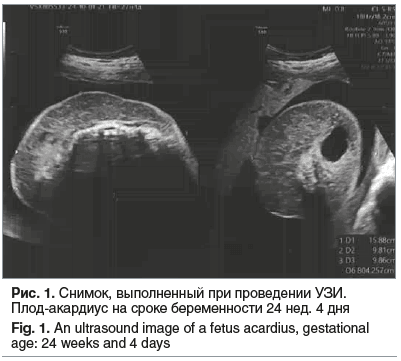

Через 1 мес. пациентка по направлению жен-ской консультации повторно госпитализирована с диагнозом «МХМА-двойня» в сроке беременности 24 нед. 4 дня, СОАП, состояние после лазерной коагуляции сосудов пуповины второго плода, рецидив кровотока в плоде-акардиусе по данным УЗИ, гестационный сахарный диабет на диетотерапии. По данным УЗ-допплерометрии в приемном отделении: 1-й плод: пульсационный индекс в артерии пуповины (PI arteria umblicalis) — 0,95(N)/0,99(N), пиковая систолическая скорость кровотока в средней мозговой артерии (MCA PSV) — 36 cм/c, пульсационный индекс в венозном протоке (PI ductus venosus) — 0,65(N). Фетометрия: предполагаемая масса плода (ПМП) — 660 г, без признаков СН; 2-й плод (рис. 1): PI arteria umblicalis — 1,75. Заключение: нарушений кровотоков первого плода не выявлено. Возобновление кровотока в артерии пуповины плода-акардиуса. Проведена профилактика респираторного дистресс-синдрома плода дексаметазоном в курсовой дозе 24 мг. На 3-и сутки госпитализации у беременной отмечена гипергликемия (уровень глюкозы плазмы 20,13 мМоль/л) и кетоацидоз. Пациентка переведена в отделение анестезиологии-реанимации, врачом-эндокринологом поставлен диагноз «сахарный диабет 2 типа», начата инсулинотерапия. Доза инсулина в дальнейшем неоднократно корректировалась до достижения целевых показателей гликемии. Пациентка стабилизирована и выписана из стационара в удовлетворительном состоянии под наблюдение врача акушера-гинеколога женской консультации.